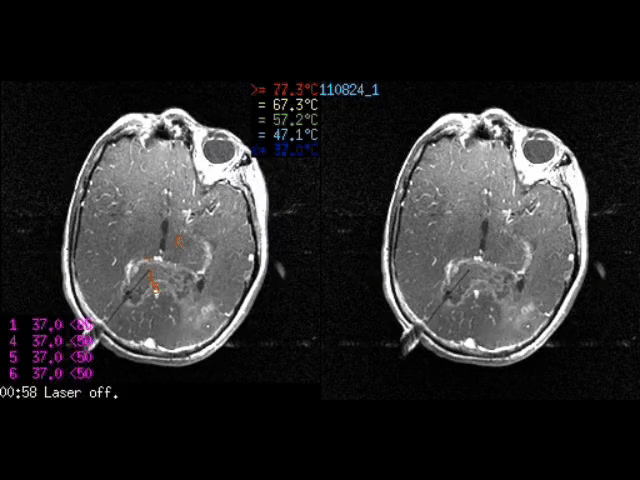

Laser Interstitial Thermal Therapy (LITT)

MRI-guided laser therapy that destroys deep or recurrent tumors through a small incision, often with same-day recovery.